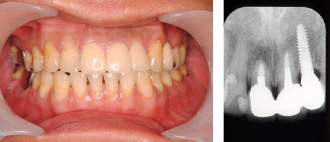

インプラント症例② ~奥歯を数本失った例~

●部分入れ歯を数年使用していたが、かみにくく、あまり使用しないとの事。

奥歯を2本以上失うと、取り外し式の入れ歯を入れないといけません。

●2本インプラントを入れました。

●固定式の歯になり、これで、よく噛めます。